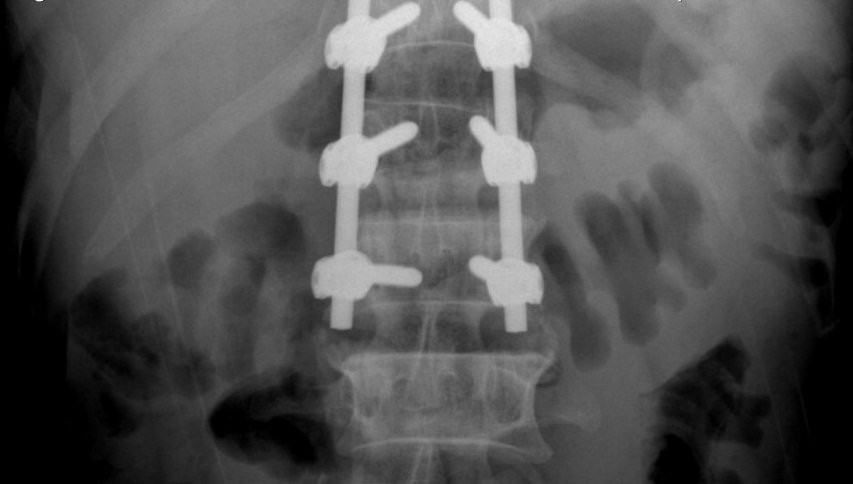

Hình ảnh X-quang sau phẫu thuật cố định cột sống cho bệnh nhân.

Các bác sỹ chỉ định cho bệnh nhân chụp XQ, CT đa dãy. Kết quả, bác sỹ chẩn đoán, bệnh nhân bị vỡ đốt sống thắt lưng L1, mất vững, thoái hóa đa tầng các đĩa đệm và đốt sống thắt lưng. Hội chẩn liên chuyên khoa được triệu tập chỉ định mổ cố định cột sống cho bệnh nhân.

Sau khi giải thích và được sự đồng thuận của gia đình bệnh nhân, các bác sỹ tiến hành phẫu thuật cố định cột sống cho bệnh nhân.